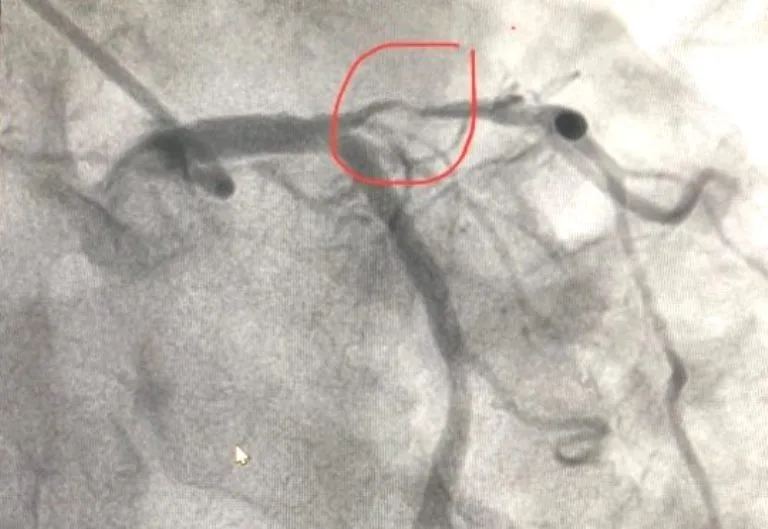

Kết quả chụp cho thấy, bệnh nhân bị hẹp gần tắc đoạn gần động mạch liên thất trước.

Lúc này, kíp can thiệp đã tiến hành nong bóng và đặt 1 stent phủ thuốc vào vị trí tổn thương. Sau khi đặt stent, người bệnh đã đỡ đau ngực, huyết áp tăng dần, giảm được thuốc vận mạch qua được cơn nguy kịch. Sau 8 ngày điều trị, người bệnh hết đau ngực, huyết áp, nhịp tim ổn định và đã được xuất viện, được chỉ định tái khám định kỳ.